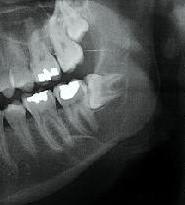

Extraction en 2004

La patiente ne revient pas après, pano demandé par un confrère en 2007 mais la patiente ne retourne pas le voir

Cadeau cette année elle vient pour faire finir 47

Pano demandé